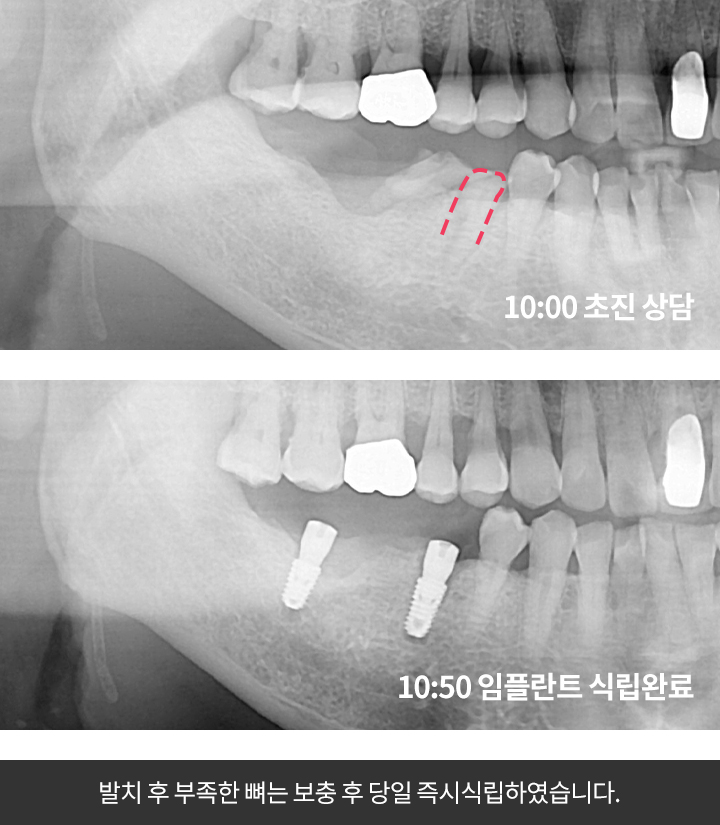

우선 CT촬영 등을 통해 구강상태를 정밀 진단 후 환자의 상태에 따라 맞는 치료 계획을 세웁니다. 구체적인 임플란트 시술 과정과 기간은 환자의 상태에 따라 달라질 수 있다고 해요.

2단계 1차 수술

이 과정은 픽스쳐를 잇몸뼈에 심는 과정인데요. (픽스쳐란 치아의 뿌리 역할을 하는 것을 말함)

이때 잇몸을 절개하는 방식과 무절개 방식 두가지가 있다고 해요.

잇몸 절개 방식은 일반적으로 많이 시술하며 잇몸을 열어 치조골에 필스쳐를 심은 뒤 절개 부위를 덮고 실로 봉합하는 방식인데요. 이 수술은 보통 1시간 정도 걸리며 수술후 1~2주뒤 수술부위가 아물면 실밥을 제거한다고 해요.

무절개 방식은 작은 구멍을 내어 고정체를 심는다고 해요. 잇몸 절개와 봉합과정이 없어 비교적 시술이 간단하고 회복기간도 빠르지만 잇몸과 잇몸뼈가 건강해야 가능한 시술이라고 해요. (뼈이식을 해야하는 경우에는 불가하다고 해요)